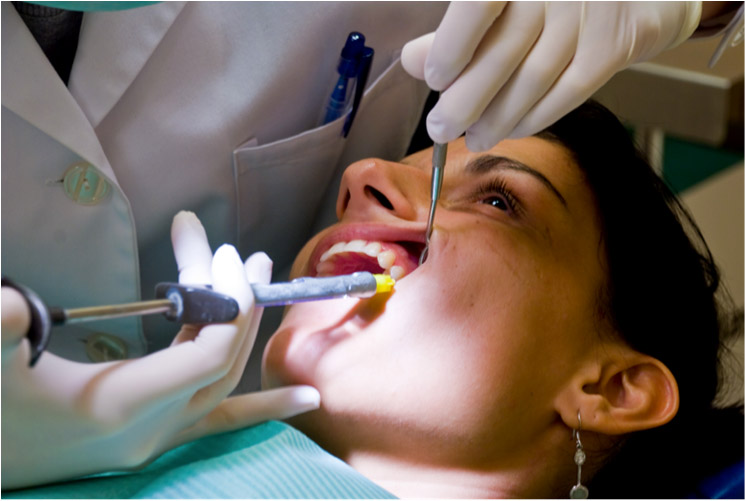

Affordable Dental Care by Top Professionals

and In Budget.

Diwan Dental Clinic provides advanced, painless and ethical dental treatments using internationally approved sterilization protocols and the latest technology. Our specialists ensure precise diagnosis, personalized plans and long-lasting oral health for every patient.

- Pain-Free Dental Experience with gentle methods and modern tools.